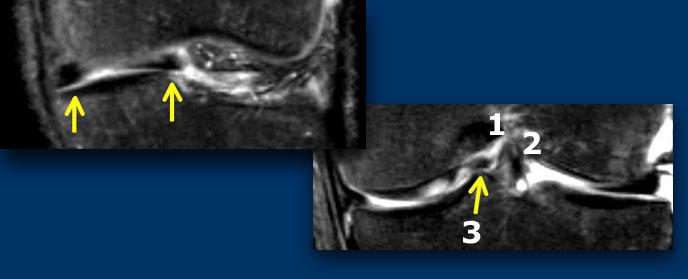

TRÁI: Phim MRI cũ có rách. Bệnh nhân đã được khâu phục hồi. PHẢI: Trên phim MRI mới, có rách mới (mũi tên vàng). Không thể xác định liệu vết rách cũ đã lành hay chưa.

Sụn chêm sau phẫu thuật 2

Bệnh nhân này đã được khâu phục hồi do rách sụn chêm.

Sau đó bệnh nhân bị chấn thương mới.

Trên phim MRI mới, không thể xác định liệu vết rách cũ đã lành hay chưa.

Tuy nhiên, phát hiện thấy rách mới, nên trường hợp này dễ chẩn đoán.

Chụp MRI-khớp: Tại vị trí rách mới, tín hiệu sáng tương đương dịch hoạt dịch (mũi tên vàng). Tại vị trí rách đã lành, tín hiệu không sáng bằng.

Trên ảnh chụp MRI-khớp, vị trí rách mới có cường độ tín hiệu rất cao tương đương dịch hoạt dịch, trong khi vị trí rách cũ đã lành chỉ có cường độ tín hiệu trung bình.

Do đó, so sánh với phim cũ giúp chẩn đoán xác định rách mới, trong khi ảnh chụp khớp cho thấy vết rách cũ đã lành.